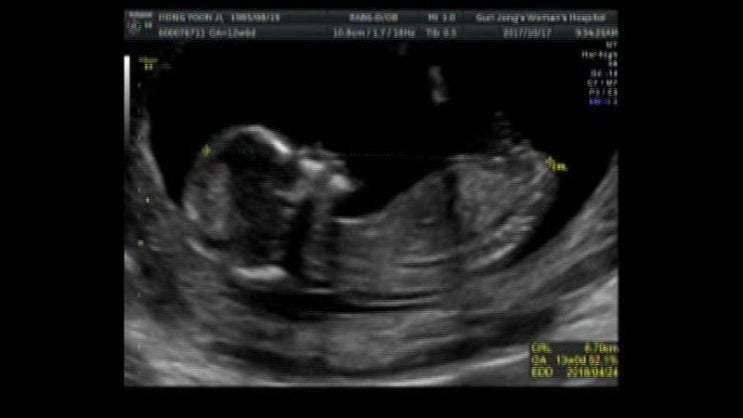

[ReRe]12w6d 1차기형아검사 + 성별

우리하람이 큰애한테 치여서 스스로 존재감 어필하느라 엄마는 헛구역질에 어질어질.. 하람아.. 그러지마.....